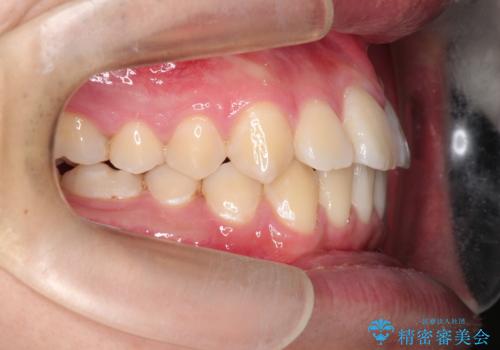

【ワイヤー矯正】前歯の凸凹を治したい。

- 前歯の凸凹を主訴に来院されました。

ワイヤー矯正は使用時間の制約がないため、マウスピースの装着管理が苦手な人には向いています。